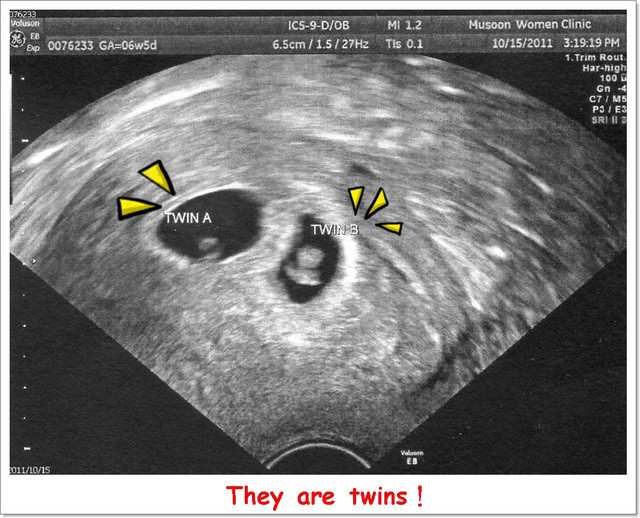

出現了讓人驚喜((嚇))的兩個胚囊,

接著,超音波師說:「還記得上禮拜來的時候我說好像有看到兩個胚囊嗎?!」

胚囊裡黑黑的就是羊水,白色的部份就是小BABY,